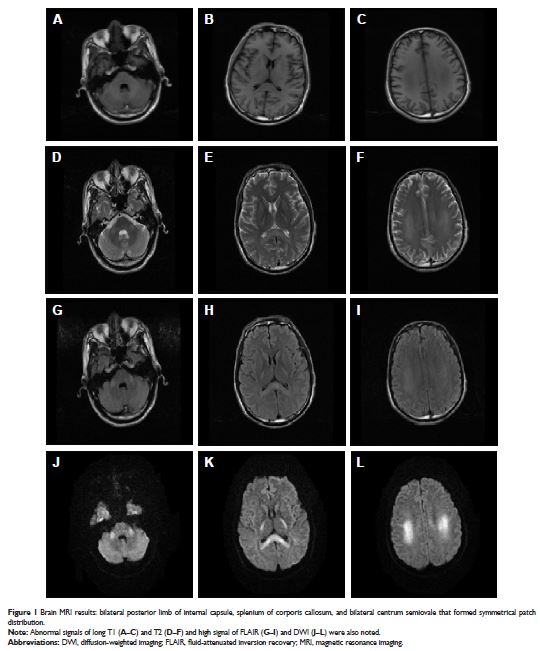

Case Report

- 作者:Meiling Wang, Yanfeng Yang, Yiwei Hou, Wenbin Ma, Rui Jia, Jinbo Chen

- 期刊:Neuropsychiatric Disease and Treatment